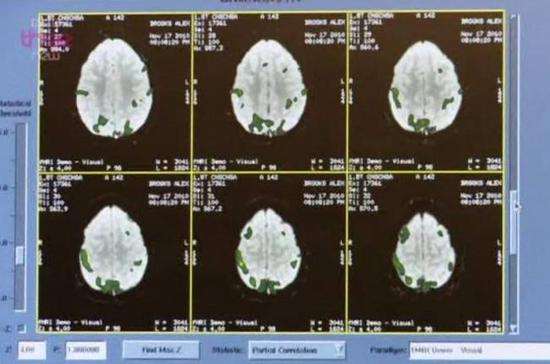

在BBC纪录片《超级品牌的秘密》中,几位神经科学专家扫描了某位果粉的大脑,发现此人看到iPhone时的脑部变化接近于信众看到耶稣像时的状态。